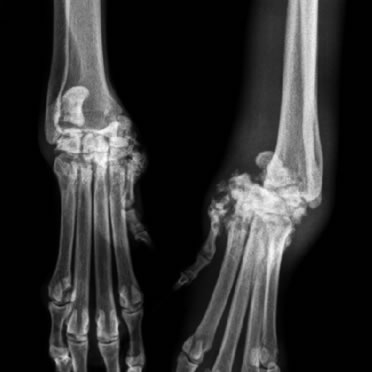

Luxação de Articulação

Deslocamento entre ossos que formam uma articulação.

Luxação de

Patela

Resultado de mal alinhamento da perna, é a “rótula” (patela) fora do lugar. É confênira e quanto antes for tratada melhores os resultados.